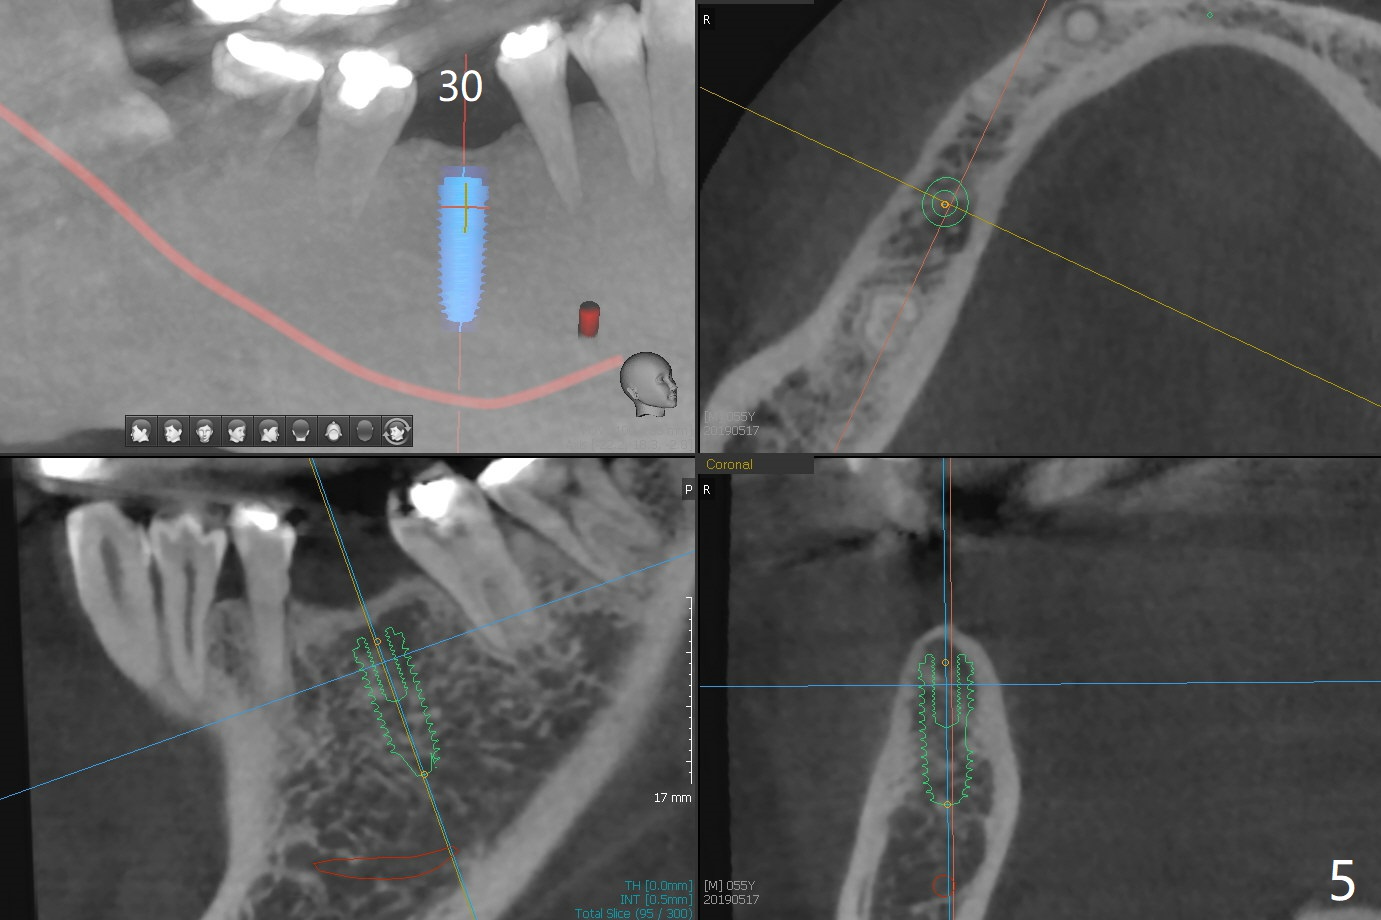

The implants at #11, 14 and 15 are IBS. To reduce the chance of screw loosening, IS guide will be used for better trajectory at #19,21,30. Since the ridge at #21 and 19 is pointed at the top, the implant will be placed deep (Fig.1-4). Bone trimmer will be used prior to pointed drill to avoid drill deflection. Check whether the IS implant driver fits IBS implant well. Try dummy implants first.